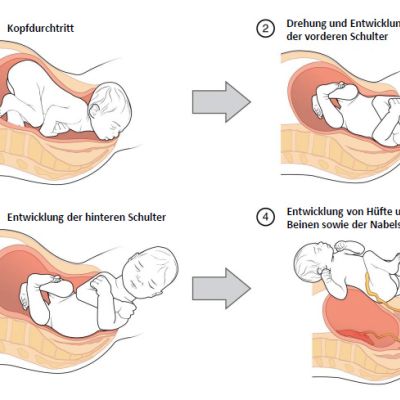

Schematische Darstellung einer Geburt in 3 Phasen: